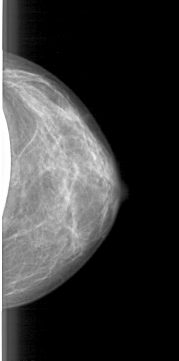

D_4085_1.RIGHT_CC

RIGHT_CC LINES 4681 PIXELS_PER_LINE 2191 BITS_PER_PIXEL 12 RESOLUTION 43.5 OVERLAY